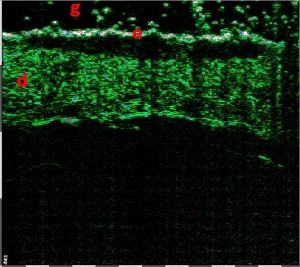

-Υπέρηχος Υψηλής Συχνότητας (HFUS) και Ιστολογία

Εφαρμογές δερματολογίας

-Κύριες εφαρμογές

-Κύριες παθολογικές διεργασίες

-Διάγνωση μορφών ακμής